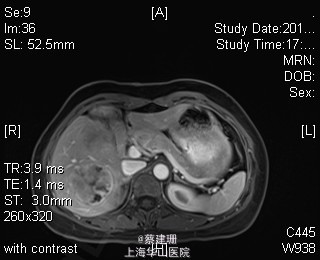

主诉:平滑肌肉瘤、肝转移癌术后,发现肝多发转移2月余。 现病史:患者3年前外院检查发现后腹膜肿瘤,外院行后腹膜肿瘤切除术后,术后病理为:平滑肌肉瘤,2013年12发现肝左叶转移癌,外院行肝左叶肿瘤切除术,术后病理为:梭行平滑肌肉瘤。2月余前患者复查发现肝脏多发转移,2015-4月肝脏MRI:肝脏多发转移。现患者无恶心、呕吐,无呕血、黑便,无皮肤巩膜黄染,无剧烈腹痛发作。现为进一步诊治收住入院。

查体:锁骨上淋巴结未扪及肿大;腹部平坦,可见陈旧性手术疤痕。未见肠型、胃型蠕动波,腹软,无压痛及反跳痛,无肌卫,肝脾肋下未及。Murphy’s 征(-),肝区叩击痛(-),肾区叩击痛(-);移动性浊音阴性。 辅查:2015-4月肝脏MRI:肝脏多发转移。

诊断 :1、多发肝转移癌 2、后腹膜平滑肌肉瘤术后 3、肝转移癌术后 处理:取右侧肋缘下切口,左侧延长,逐层切开进腹,探查腹腔:见上腹部粘连,仔细游离上腹部腹腔粘连,探查见无腹水,胃、肠、胰、脾及盆腔脏器未及异常,腹腔未见明显转移结节;肝脏无硬化。肝门淋巴结无肿大,门静脉主干无栓子。肿瘤多枚,最大两枚位于肝右叶VI段,肿瘤大小约7*6*5cm。V段肿瘤直径约5cm。左内叶肿瘤多枚,直径0.5-4cm,紧贴第一肝门。左外叶肿瘤多枚,直径1-3cm,肿块质韧,边界尚清,有包膜。术中诊断为转移性肝癌,决定行左半肝切除,肝右叶特殊肝段切除。